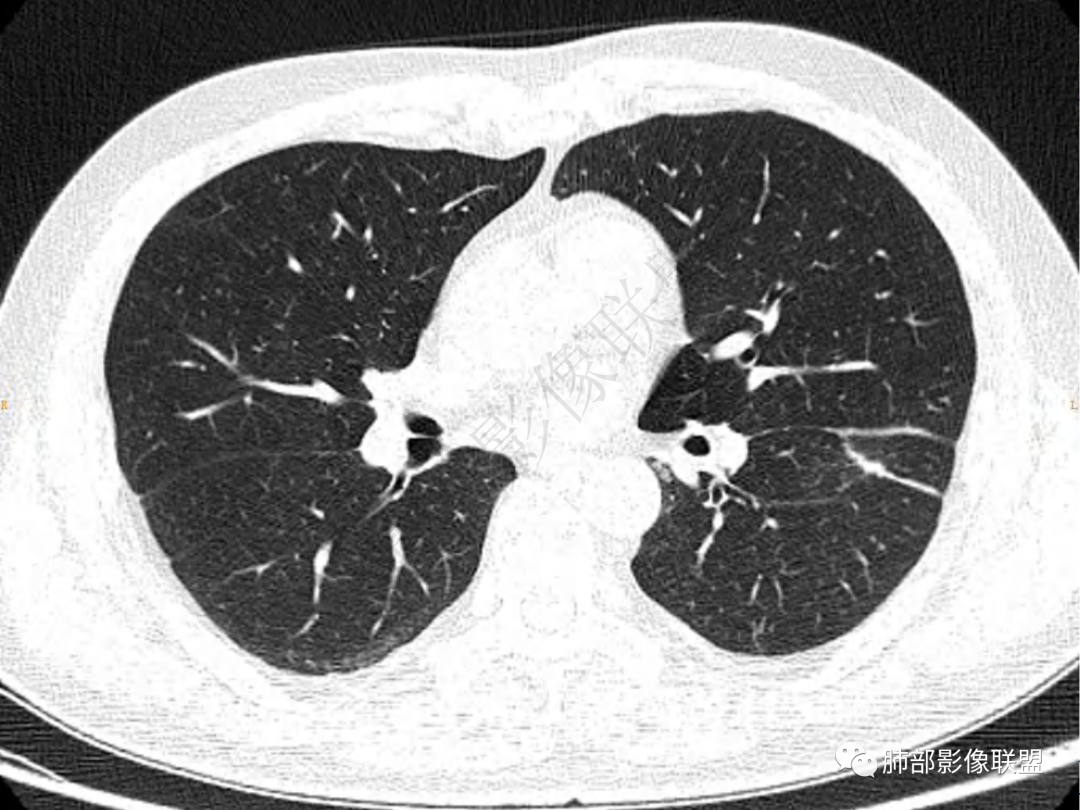

1.中年男性,咳嗽咳痰20余天,间断咯血2周

2.左肺下叶团片影,跨背段及内前基底段,实性部分类椭圆形,密度不甚均匀,可见毛刺及棘状突起,未见典型分叶及胸膜凹陷。病灶上下缘可见相应肺段支气管旁进侧出,管壁轻度增厚,未见狭窄阻塞。

3.周边较大范围磨玻璃影,边界相当模糊,小叶增厚明显。注意叶裂另一侧、左肺舌段亦可见磨玻璃影及增厚的小叶间隔。未见明确卫星病灶。

4.实性部分不均匀环形强化并显示一小范围低密度坏死区或空洞。较之肺窗,整体纵隔窗范围较小,提示病灶并不十分密实。抑或为不同时段图像。

5.双肺门及纵隔未见增大淋巴结。未见胸腔积液。